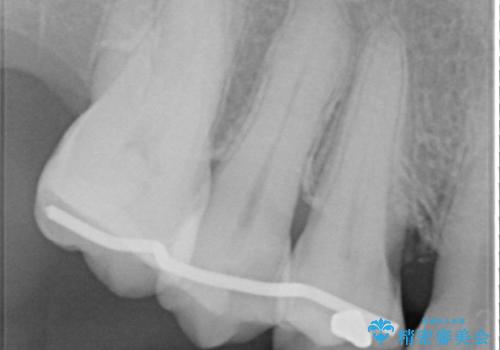

検査の結果、強い歯ぎしりによる歯の周囲の骨の吸収が認められたため歯槽骨の再生・歯周ポケットの除去・力に対抗する連結補綴・補綴前処置としての小矯正を計画します。

特定の歯に強く力がかかりまた歯周病により臨床歯根が短くなっているような場合、歯の動揺を抑えるため連結補綴が検討されます。

歯の動揺が続くとより周囲の骨を失い最終的には歯を喪失してしまう可能性が高くなってしまうためです。

今回連結補綴を行うにあたり、歯周病の問題を解決するために再生療法・歯周ポケット除去手術を、またより歯の神経を保存し力に対抗できる環境を整えるために小矯正を行い精度の高いメタルボンドクラウンを製作することができました。